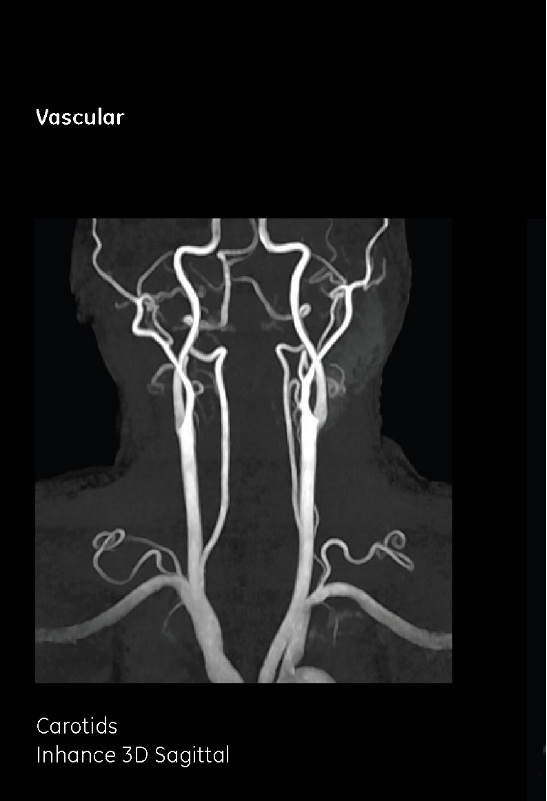

六、血管成像

磁共振管成像(MRA)分為非增強MRA與增強MRA兩種,非增強MRA具有無創(chuàng)、無輻射的特點,不受骨質偽影影響,顱底動脈環(huán)顯示良好,可清晰顯示顱內動脈瘤的位置、毗鄰關系等;可評估全身動脈病變,準確診斷動脈瘤、動脈夾層、下肢動脈閉塞癥、肺動脈栓塞等,是安全、無創(chuàng)的檢查方法。增強MRA對血管狹窄的反映程度比較真實,其可靠性與傳統(tǒng)DSA相仿。